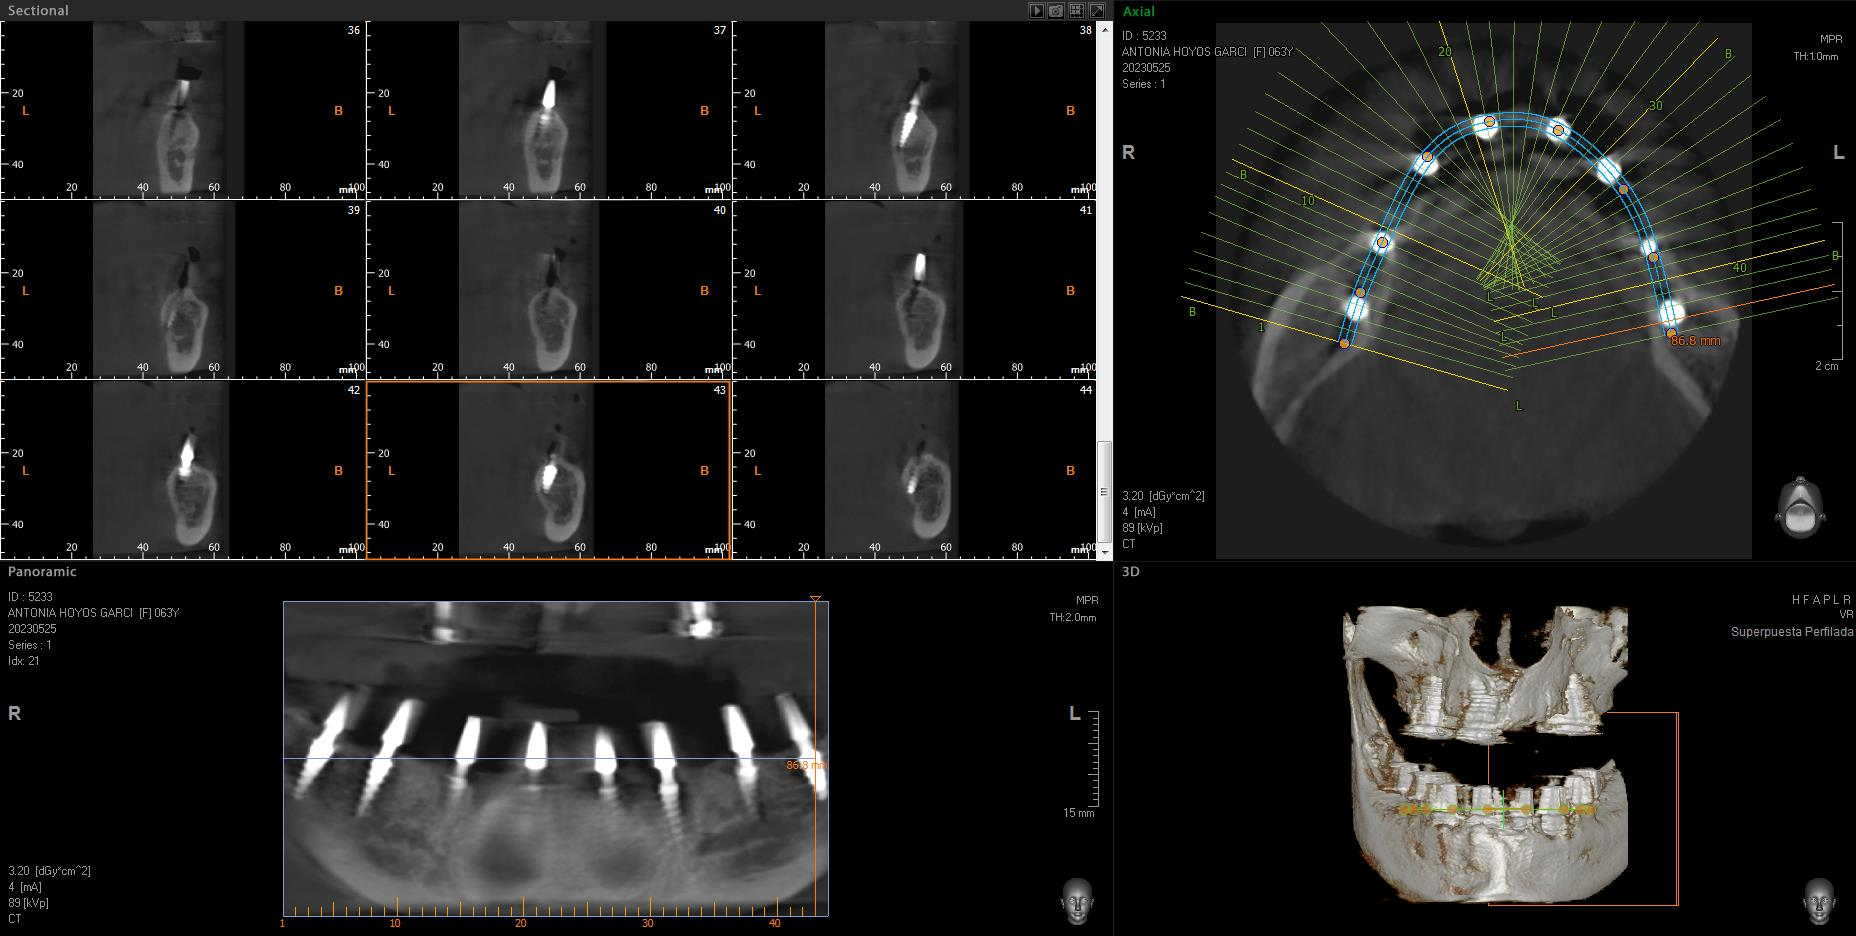

Implantes SLD-c

Secuencia de imágenes RX, antes y después de la inserción de implantes SLD-c en la parte inferior de la boca.

Paciente mujer de 65 años.

- Radiografía previa a la operación.

- Colocación implantes Radhex SLD-c parte inferior.

- Colocación implantes Radhex SLD-c parte inferior con soldadura.